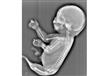

جنين على شكل عروس البحر

ولفتت الصحيفة في تقرير لها، اليوم الخميس، إلى أن الأم الصينية كانت في الشهر السادس من الحمل عندما قام الأطباء بفحصها في مدينة ياتشنج وسط الصين، ليتم اكتشاف وجود ذيل ينمو لجنينها وليس أقدام، مشيرة إلى قول الأطباء: إن الجنين تعرض لحالة التصاق قدمين تجعلهما أشبه بذيل السمكة.

وتابعت أن الطفل في هذه الحالة يكون له رأس وجسد إنسان وذيل في صورة تشبه عروس البحر، مشيرة إلى أن المتخصصون توقعوا ألا يتسمر الجنين على قيد الحياة بعد ولادته إلا ساعات قليلة.